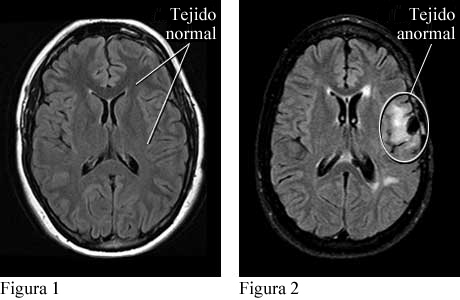

Resonancia magnética de convulsiones